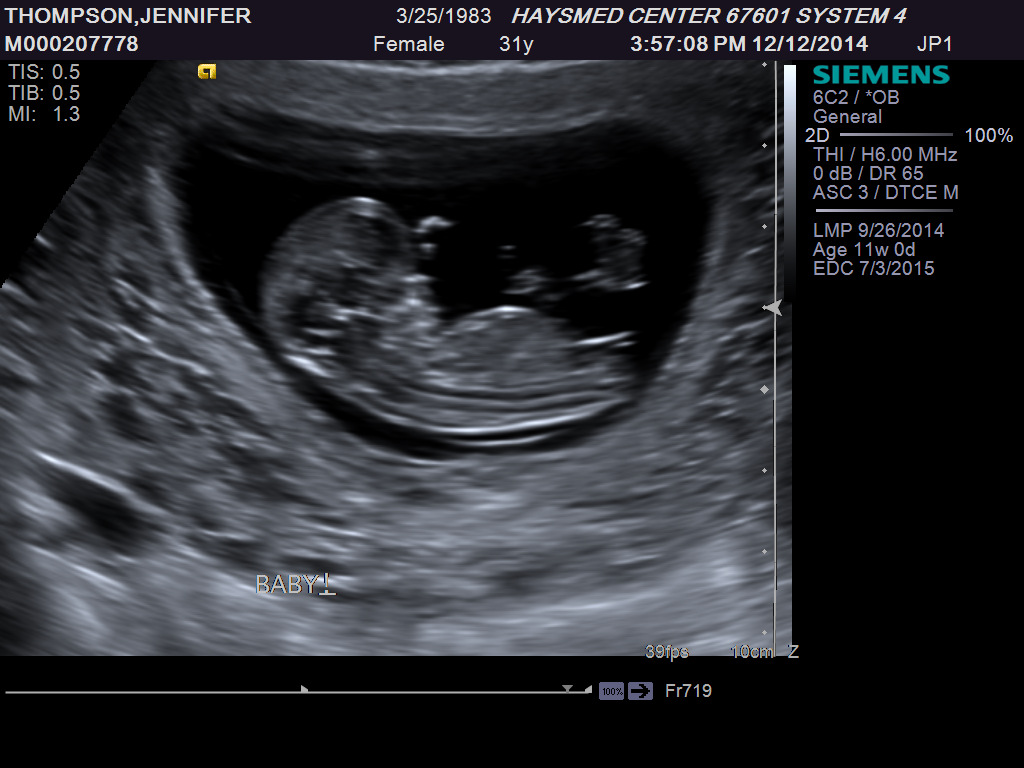

My current experience is that I continue to get hungrier and hungrier, but I have less and less space to hold anything extra. That’s good, because my baby is growing big and strong, but it is getting more uncomfortable every day. Even though I am feeling less and less like myself, I am very excited that our last ultrasound showed that we are having a little boy.